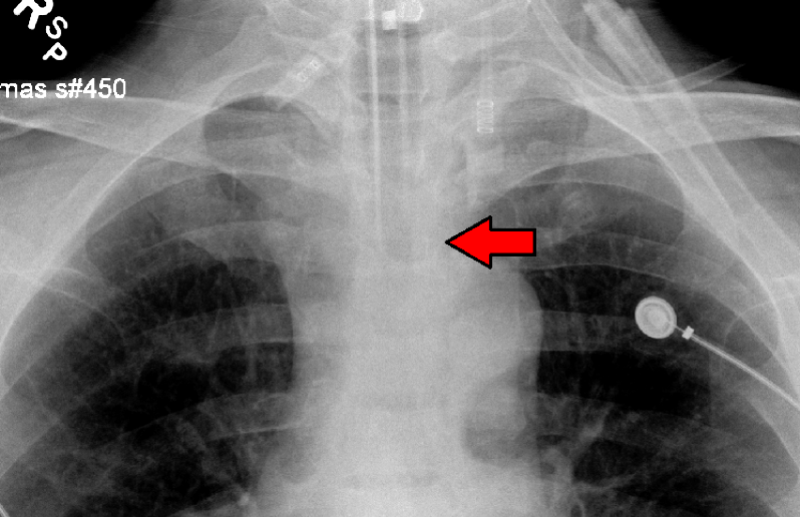

Preview Image: Intubation Tube in Position